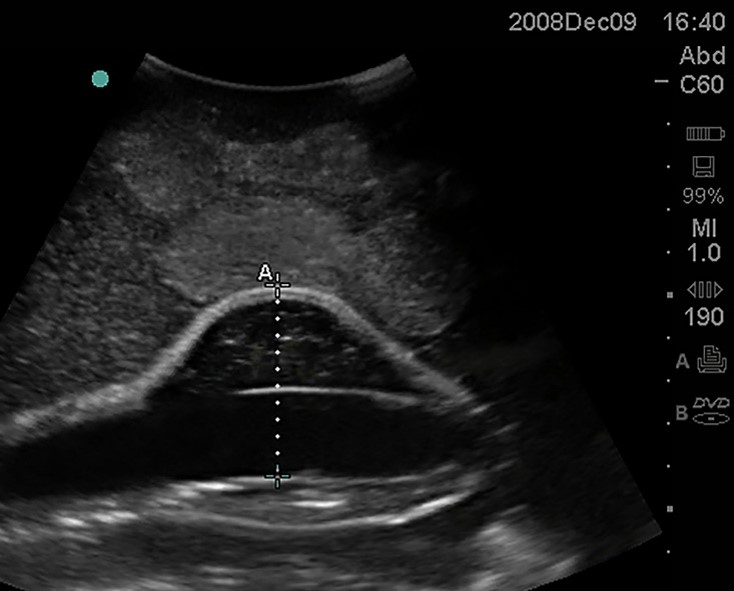

<p>In this sagittal plane, what is this structure?</p>

In this sagittal plane, what is this structure?

Aorta

IVC